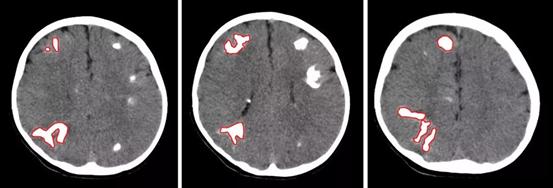

术前CT,红圈标注为不同角度下的右侧脑部4个大结节

通过脑CT及核磁共振检查结果发现闳闳脑内长满了结节点,密密麻麻多达数百个,大的有鸡蛋大小,小的如玉米粒般,布满了整个脑部。在充分研判了患儿病情后,神经外科一病区主任关宇团队决定实施外科手术治疗。

8月31日,关宇光团队为闳闳进行了手术,右侧脑部4个大的结节点被成功切除,术后患儿情况稳定,恢复良好,最让家长担心的癫痫发作也得到了有效改善,即使发热高烧到39°C,也不会出现癫痫抽搐发作,多年的心结终于放下。

术后CT示意图,右侧脑部4个大结节点(灰色阴影部分)被成功切除